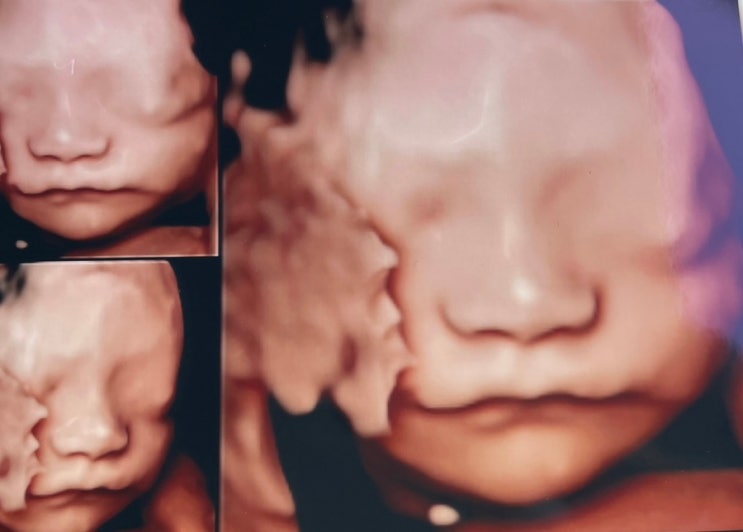

임신 22~25주 증상, 입체초음파 아기 얼굴 보고오기 / 임산부 B형간염 접종

안녕하세요 :) 어느덧 임신 7개월에 접어들었네요. 이제 몸도 많이 무거워져서 꽤나 힘들어진 것 같아요. 7...